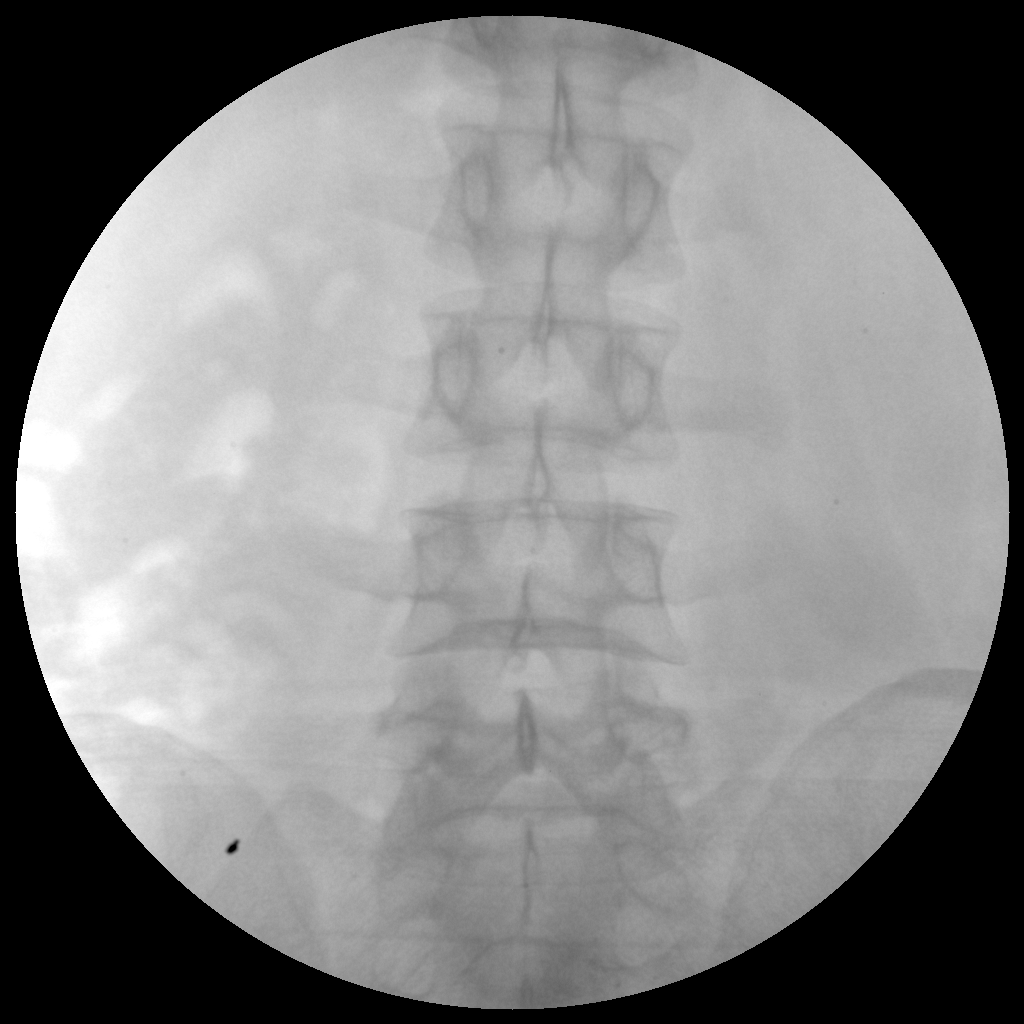

●經(jīng)典影像工作站,可隔室操作避免輻射

●全數(shù)字化百萬(wàn)像素影像系統(tǒng),圖像清晰

●靈活的C臂機(jī)架設(shè)計(jì),滿足臨床大范圍運(yùn)動(dòng)